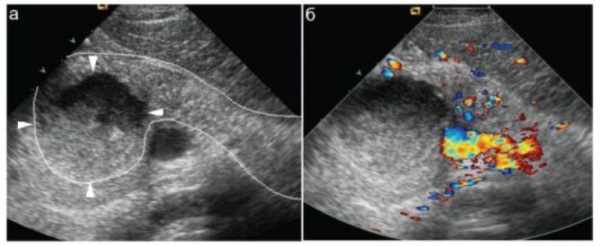

(Левый) На поперечном УЗ срезе в хвосте поджелудочной железы определяется сложной формы однокамерная псевдокиста, содержащая эхогенный детритЕЗ, вероятно, кровь. Обратите внимание на отбрасываемую псевдокистой легкую тень.

(Правый) Тот же пациент, КТ с контрастным усилением, аксиальная томограмма. Хотя псевдокиста визуализируется прекрасно, содержащийся в ее просвете детрит, хорошо видимый при УЗИ, едва различим.